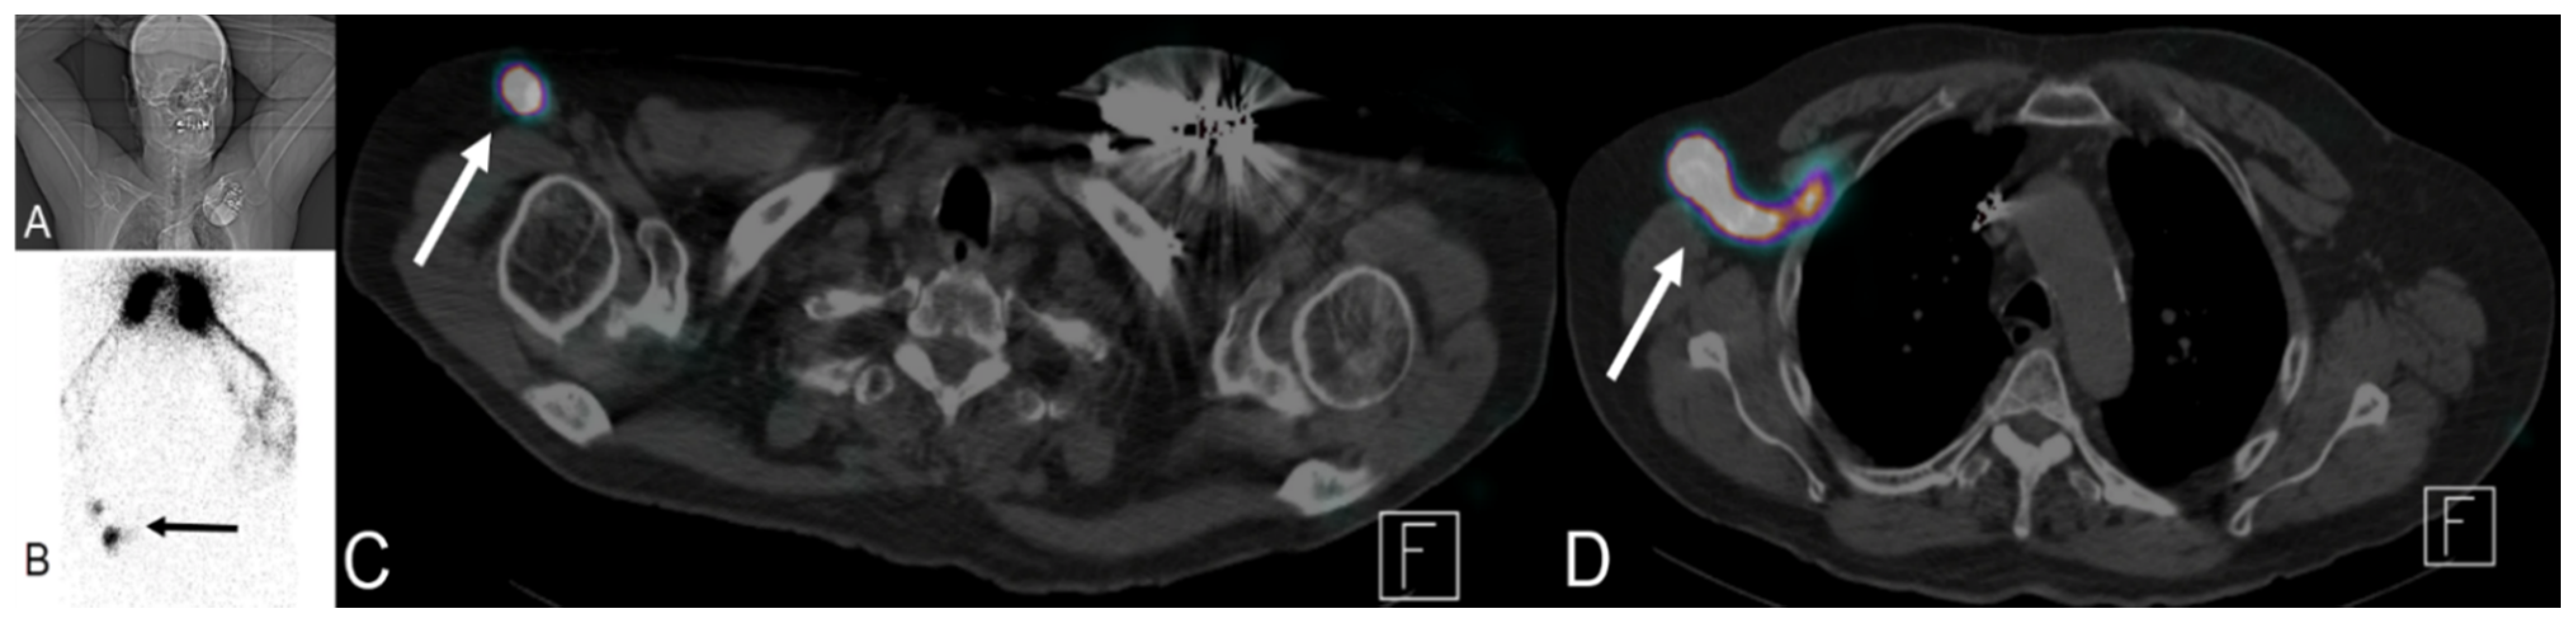

Lymphoscintigraphy